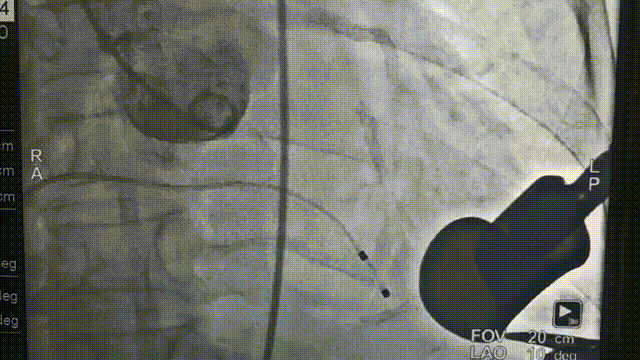

全麻后,首先在心前区的肋间切开3-4CM小切口,暴露心脏的心尖位置,心尖穿刺后进入导丝,利用导丝交换导管鞘完成通路建立。将系统送入左心房,顺利到达二尖瓣病变区域。在经食道超声引导下,术者通过反复评估二尖瓣反流位置、抓捕位置、反流程度,在2区主动脉瓣与二尖瓣闭合线垂直进行巧妙夹合,最终植入一枚ValveClamp®MVC-Ⅲf夹。超声评估夹子固定良好,组织桥完整,无葫芦征,位置、轴向均符合预期。患者术后反流程度从大量转至少量,手术取得圆满成功。患者恢复良好,已经顺利出院。

J-valve瓣膜释放前造影 猪尾导管造影确定瓣环平面